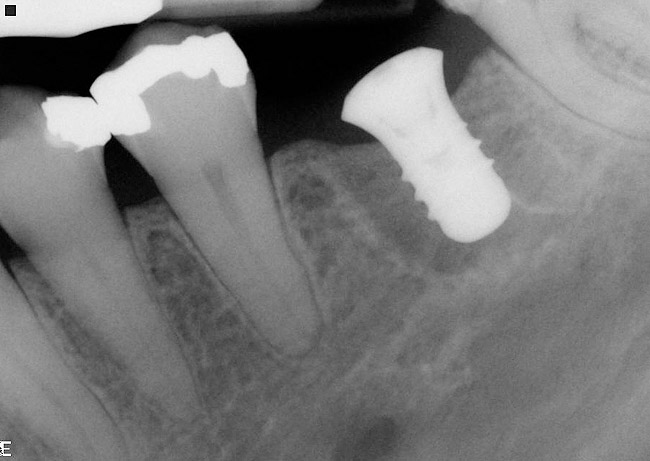

Implant placement at the time of mandibular molar extraction should never be attempted if there is any doubt about the ability to place an ideal dimension implant in the appropriate restorative position and attain primary stability. In such a situation it is better to first perform regenerative therapy at the time of tooth removal and place the implant in a subsequent surgical session (Figure 2 through Figure 4).

If the most crestal aspect of the interradicular bone is at least 3-mm-wide mesio-distally: A 2.2-mm-wide guide bur is drilled to the appropriate length, a guide pin is inserted, and a radiograph is taken (Figure 7). If necessary, the initial osteotomy is extended apically. A tapered osteotome is inserted into the osteotomy and moved mesio-distally and bucco-lingually to expand the osteotomy site. A 2.8-mm bur is used to prepare the osteotomy to depth, and a 2.8-mm-wide tapered osteotome is inserted in the osteotomy and once again utilized in mesio-distal and bucco-lingual directions to expand the osteotomy site. If the mesial and distal aspects of the interradicular bone are still intact at this point, a 3.5-mm bur is utilized to prepare the osteotomy to depth. A 3.5-mm-wide osteotome is inserted into the osteotomy and utilized in the manner already described. A decision is made as to whether to place a tapered implant with a 4.1-mm-wide base and a 6.5-mm-wide neck, or to use a 4.8-mm-wide bur and prepare the osteotomy to depth, in anticipation of placement of an implant with a 4.8-mm-wide parallel wall body and a 6.5-mm-wide platform. The chosen implant is inserted into the osteotomy (Figure 8), appropriate regenerative materials are placed, and the flaps are sutured. Following maturation of the regenerating hard tissues, the implant is ready for restoration (Figure 9). A radiograph taken 54 months after implant restoration demonstrates stability of the peri-implant crestal bone (Figure 10).